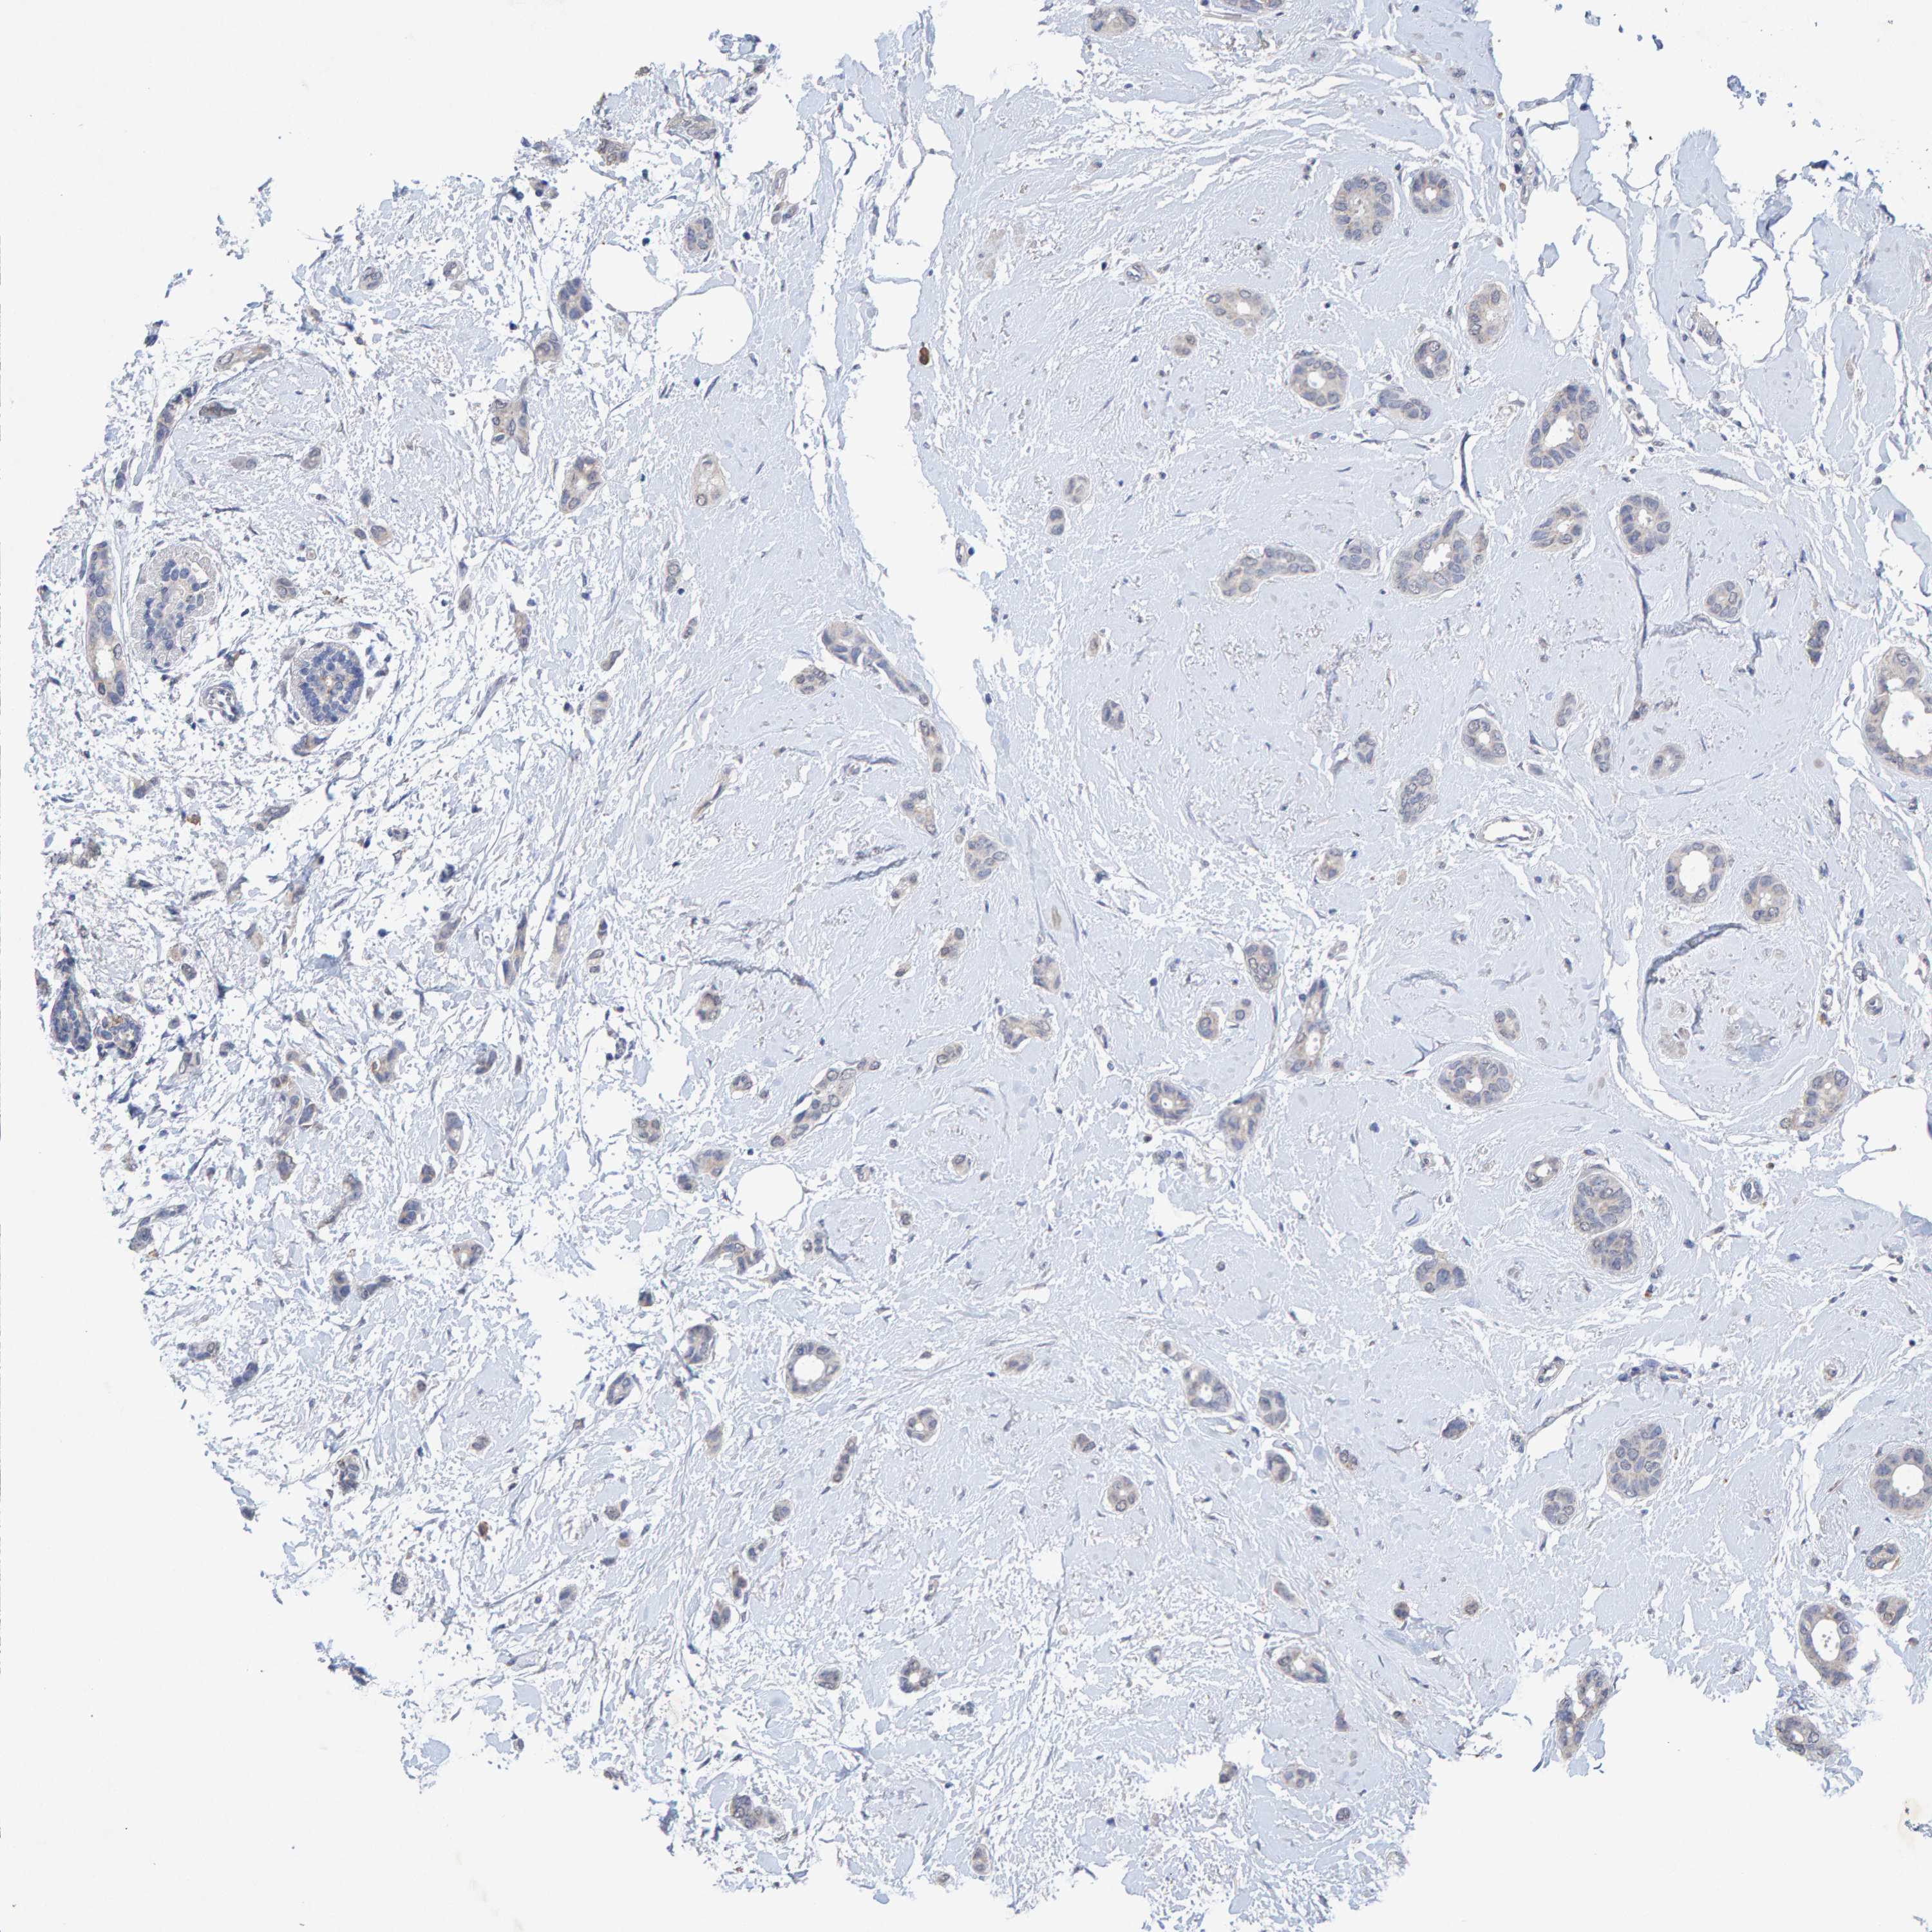

BRCA TCGA BRCA VALIDATION PROTEIN EXPRESSION

ANTIBODIES

AND

VALIDATION